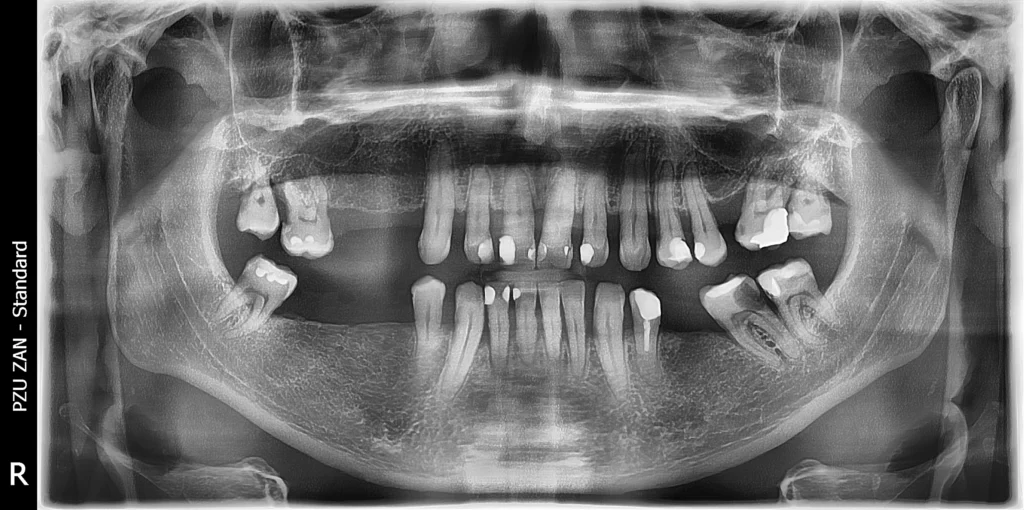

Following a healing period of six months, during which full integration of the implants occurred, the patient returned for the final phase. We performed new intraoral scans and detailed analysis to ensure perfect accuracy and fit.

The final result was achieved using high-quality monolithic zirconia restorations—delivering a strong, natural-looking, and long-lasting smile.